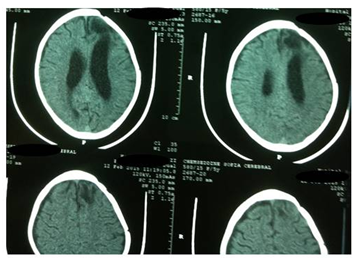

An eight-year-old girl underwent surgery for the removal of an intracerebral frontal left hydatid cyst three years ago. She didn’t take any regular medical therapy following surgery. She came with intermittent headaches and vomiting for two months. There was no history of recent trauma. Physical examination revealed a healthy child in no distress. There was no frontal syndrome. Chest X rays and abdomen ultrasonography were normal. CT scan revealed a relatively large left frontal cystic lesion of similar density to cerebro-spinal fluid, with another small separate one in the epidural space in the adjacent region close to the midline, associated to bone exostosis around the cyst without bone defect (Figure 1). No rim enhancement was seen. Laboratory tests were normal. The patient underwent a left frontal craniotomy which revealed intracerebral and epidural hydatid cysts (Figure 2). The intracerebral cyst was completely removed following the Dowling’s technique, whereas the epidural one ruptured because It was seen that the inner part of the cranium overlying the cyst was thickened and the membrane of the cyst was adherent to the cranium. The contents of the cyst aspirated without any contagion and the cavities were irrigated with warm hypertonic saline solution. The epidural cyst membrane removed totally and dura underlying was normal. The dinner table was eroded by the mass without total defect. There was no evidence to suggest that both cysts communicate between each other. The postoperative course of the patient was uneventful. CT scan control showed a complete removal of the two cysts without recurrence (Figure 3). Following the surgery, the patient received oral Albendazole (15mg/kg/day). She is doing well at 6months follow-up.

Figure 2 Intra-operative photograph of the intact epidural hydatid cyst below the frontal bone (blue arrow).